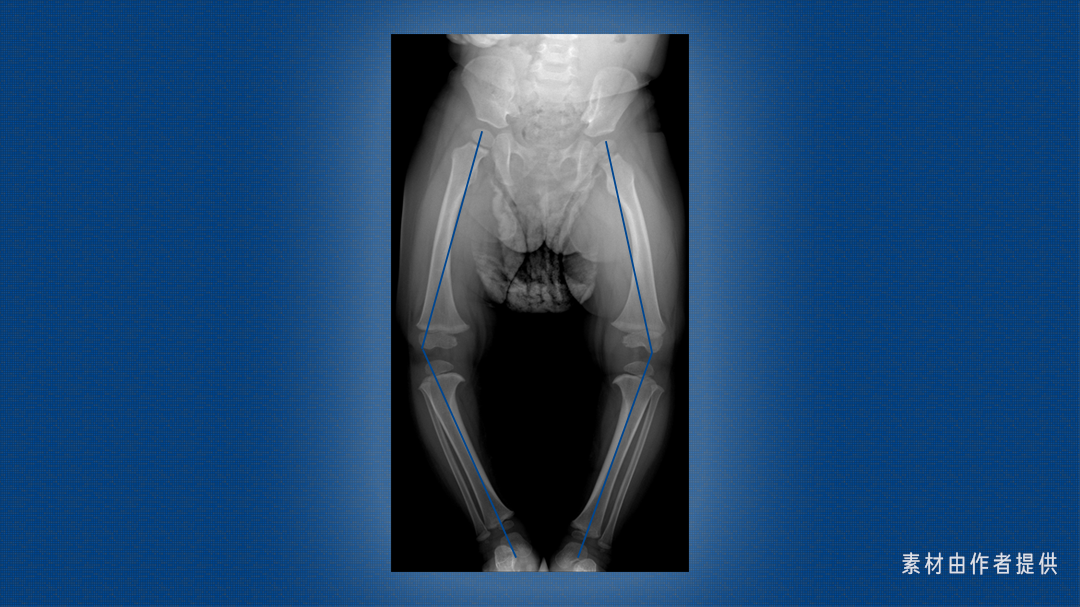

这是一双 X 型腿,医学上称为「膝外翻」,大腿和小腿轴线的交点偏向身体中轴线。

这是一双 O 型腿,也叫「膝内翻」,大腿和小腿轴线的交点偏离身体中轴线。

生理性膝内翻或膝外翻的变化趋势一定是两侧对称的,且身高发育、运动能力正常,除了腿看着不太直,没有疼痛等其它症状。

而在 7 岁之后,如果只有一侧膝内翻或膝外翻,甚至出现双腿不等长,走路姿势异常,容易跌倒,足部和膝关节肿胀、疼痛或局部皮肤温度升高这类现象,这下要提高警惕了。